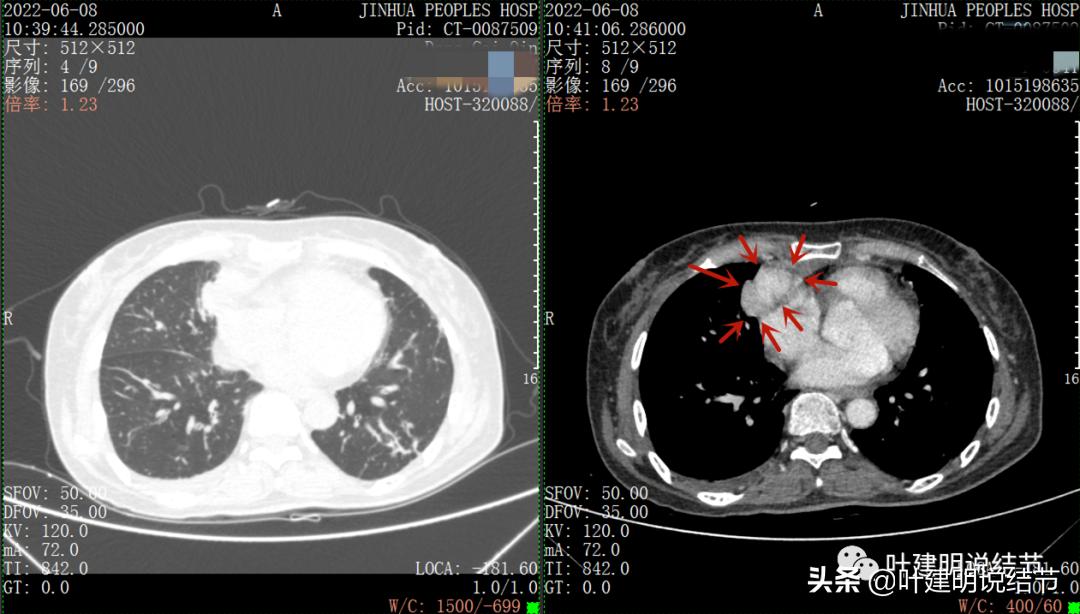

再来看看她的CT增强图像:

以下图片左侧是肺窗,右侧是纵隔窗。红色箭头示病灶,桔色箭头示无名静脉,黄色箭头示支气管,砖色箭头示上腔静脉,蓝色箭头示主动脉,紫色箭头示肺动脉。

病灶纵隔胸膜侧非常光滑,说明来源于纵隔

粉色箭头示淋巴结可能